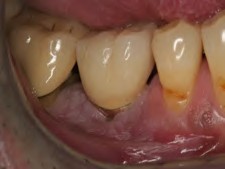

Fig 15. Pretreatment view of a male patient who presented with peri-implantitis after being told by three specialists that the implant would need to be removed.

Figure 15

Fig 16. A circumferential defect of 10 mm to 11 mm was confirmed, and the patient was advised that a technique would be used to treat him but that multiple surgeries and procedures may be required.

Figure 16

Fig 17. The implant had a 12-mm mesial pocket depth, a 12-mm distal pocket depth, bleeding on probing, and perioral exudate.

Figure 17